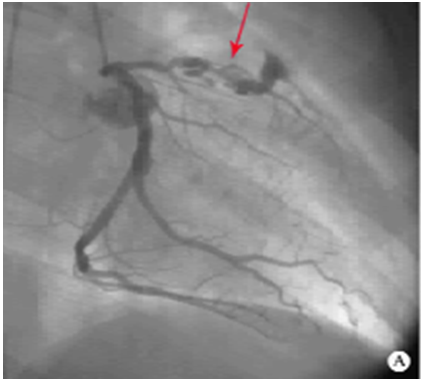

CoronaryAngiography (冠状动脉造影)

左前降支巨大冠脉瘤内有血栓,远端狭窄

Findingsin coronary artery bypass grafting

(冠状动脉搭桥术中所见)

冠状动脉瘤样扩张